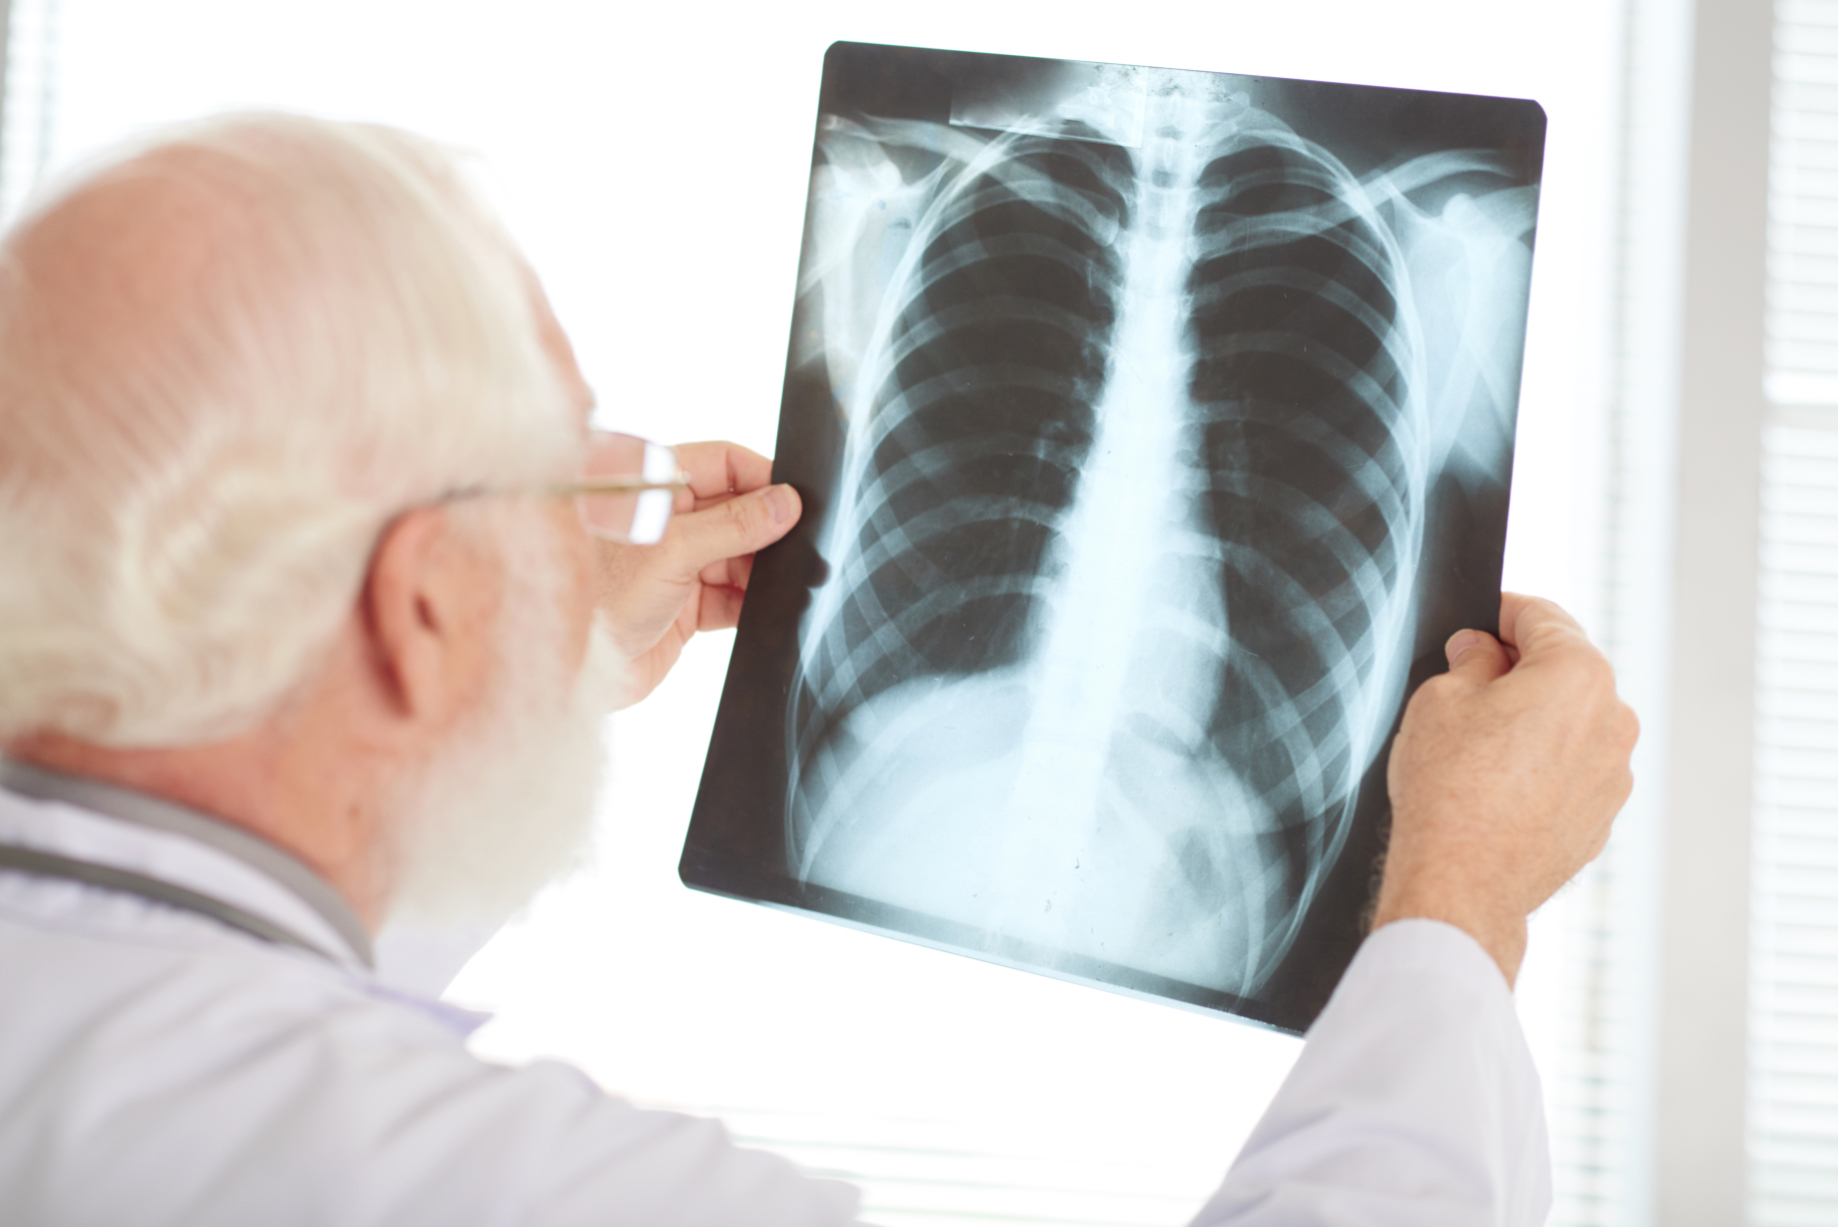

Dokładna diagnostyka to podstawa skutecznego leczenia. W naszej placówce wykonujemy kompleksowe badania, które pozwalają precyzyjnie określić przyczynę dolegliwości. Spirometria ocenia wydolność płuc i przepływ powietrza przez drogi oddechowe. RTG klatki piersiowej wykrywa zmiany w strukturze płuc i opłucnej.